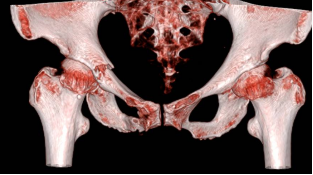

李女士因一次意外,造成右侧锁骨和骨盆骨折,由缪博主任团队收治到创伤中心病房。李女士基础疾病较多,有严重的高血压、缺血性心脏病,还接受过冠脉支架手术。而且,李女士的骨质疏松严重,右锁骨发生了远端和近端双骨折的少见情况,骨盆也是耻骨上下支骨折合并髋臼前柱骨折。坚强的李女士对于自己的伤情并没有恐惧,反而是勇敢地迎接病魔的挑战,为了能更好的恢复运动功能,提高今后的生活质量,她毅然决定接受手术治疗。对于在锁骨的两端各固定一枚钢板,她完全能够接受;但是对于骨盆骨折外固定架固定的手术方案,她却犹豫了。但是李女士的骨盆骨折较为不稳定,且髋臼前柱骨折位于负重区,如果采用保守治疗,必须长期绝对卧床,发生VTE及其他并发症的风险很高。

缪博副主任医师带领医疗团队根据李女士的实际情况,结合目前国内的先进的治疗手段,为她量身制定了微创通道螺钉内固定耻骨上支和髋臼前柱骨折的治疗方案。目前,通道螺钉技术是国内刚刚兴起的微创手术技术,它对于手术者的技术要求非常高。手术医生要在患者的直径仅有1~1.5cm的且带有一定弧度和斜度的耻骨上支精准地打入一枚直径为6.5mm,长度为100mm以上的螺钉,稍有不慎就会损伤到耻骨支前方腹股沟韧带内穿行的股血管和股神经,造成不可收拾的结果,而完成这么复杂而精准的手术,仅仅需要在患者耻骨结节下方切一个1cm左右的小切口。目前我省只有几位骨创科专家掌握这项技术,还有几个兄弟医院正在使用手术机器人引导下摸索学习和实践这一新技术。缪博副主任医师和医疗团队的医师们,凭借扎实的微创内固定技术和对骨盆解剖结构的熟练掌握,仅在普通的术中C型臂透视引导下,用时1个小时左右,顺利完成了我院第一例通道螺钉微创内固定骨盆骨折的手术。而且,我院这例手术不但固定了耻骨上支骨折,还固定了髋臼前柱骨折,难度更高,这也是对于通道螺钉技术的一次新的尝试和突破。